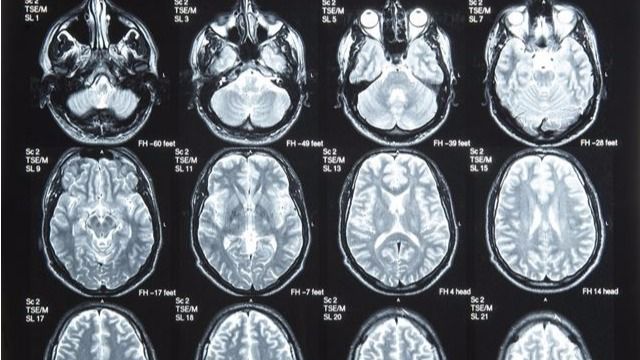

En España se diagnostican 3.500 nuevos casos de tumores cerebrales y, en el caso de la metástasis cerebral, la cifra aumenta a los 14.000 casos. En el caso de los tumores cerebrales, se desconocen las causas que pueden originarlos, aunque se valoran en su desarrollo los factores genéticos, ambientales, virus, radiaciones y traumatismos.